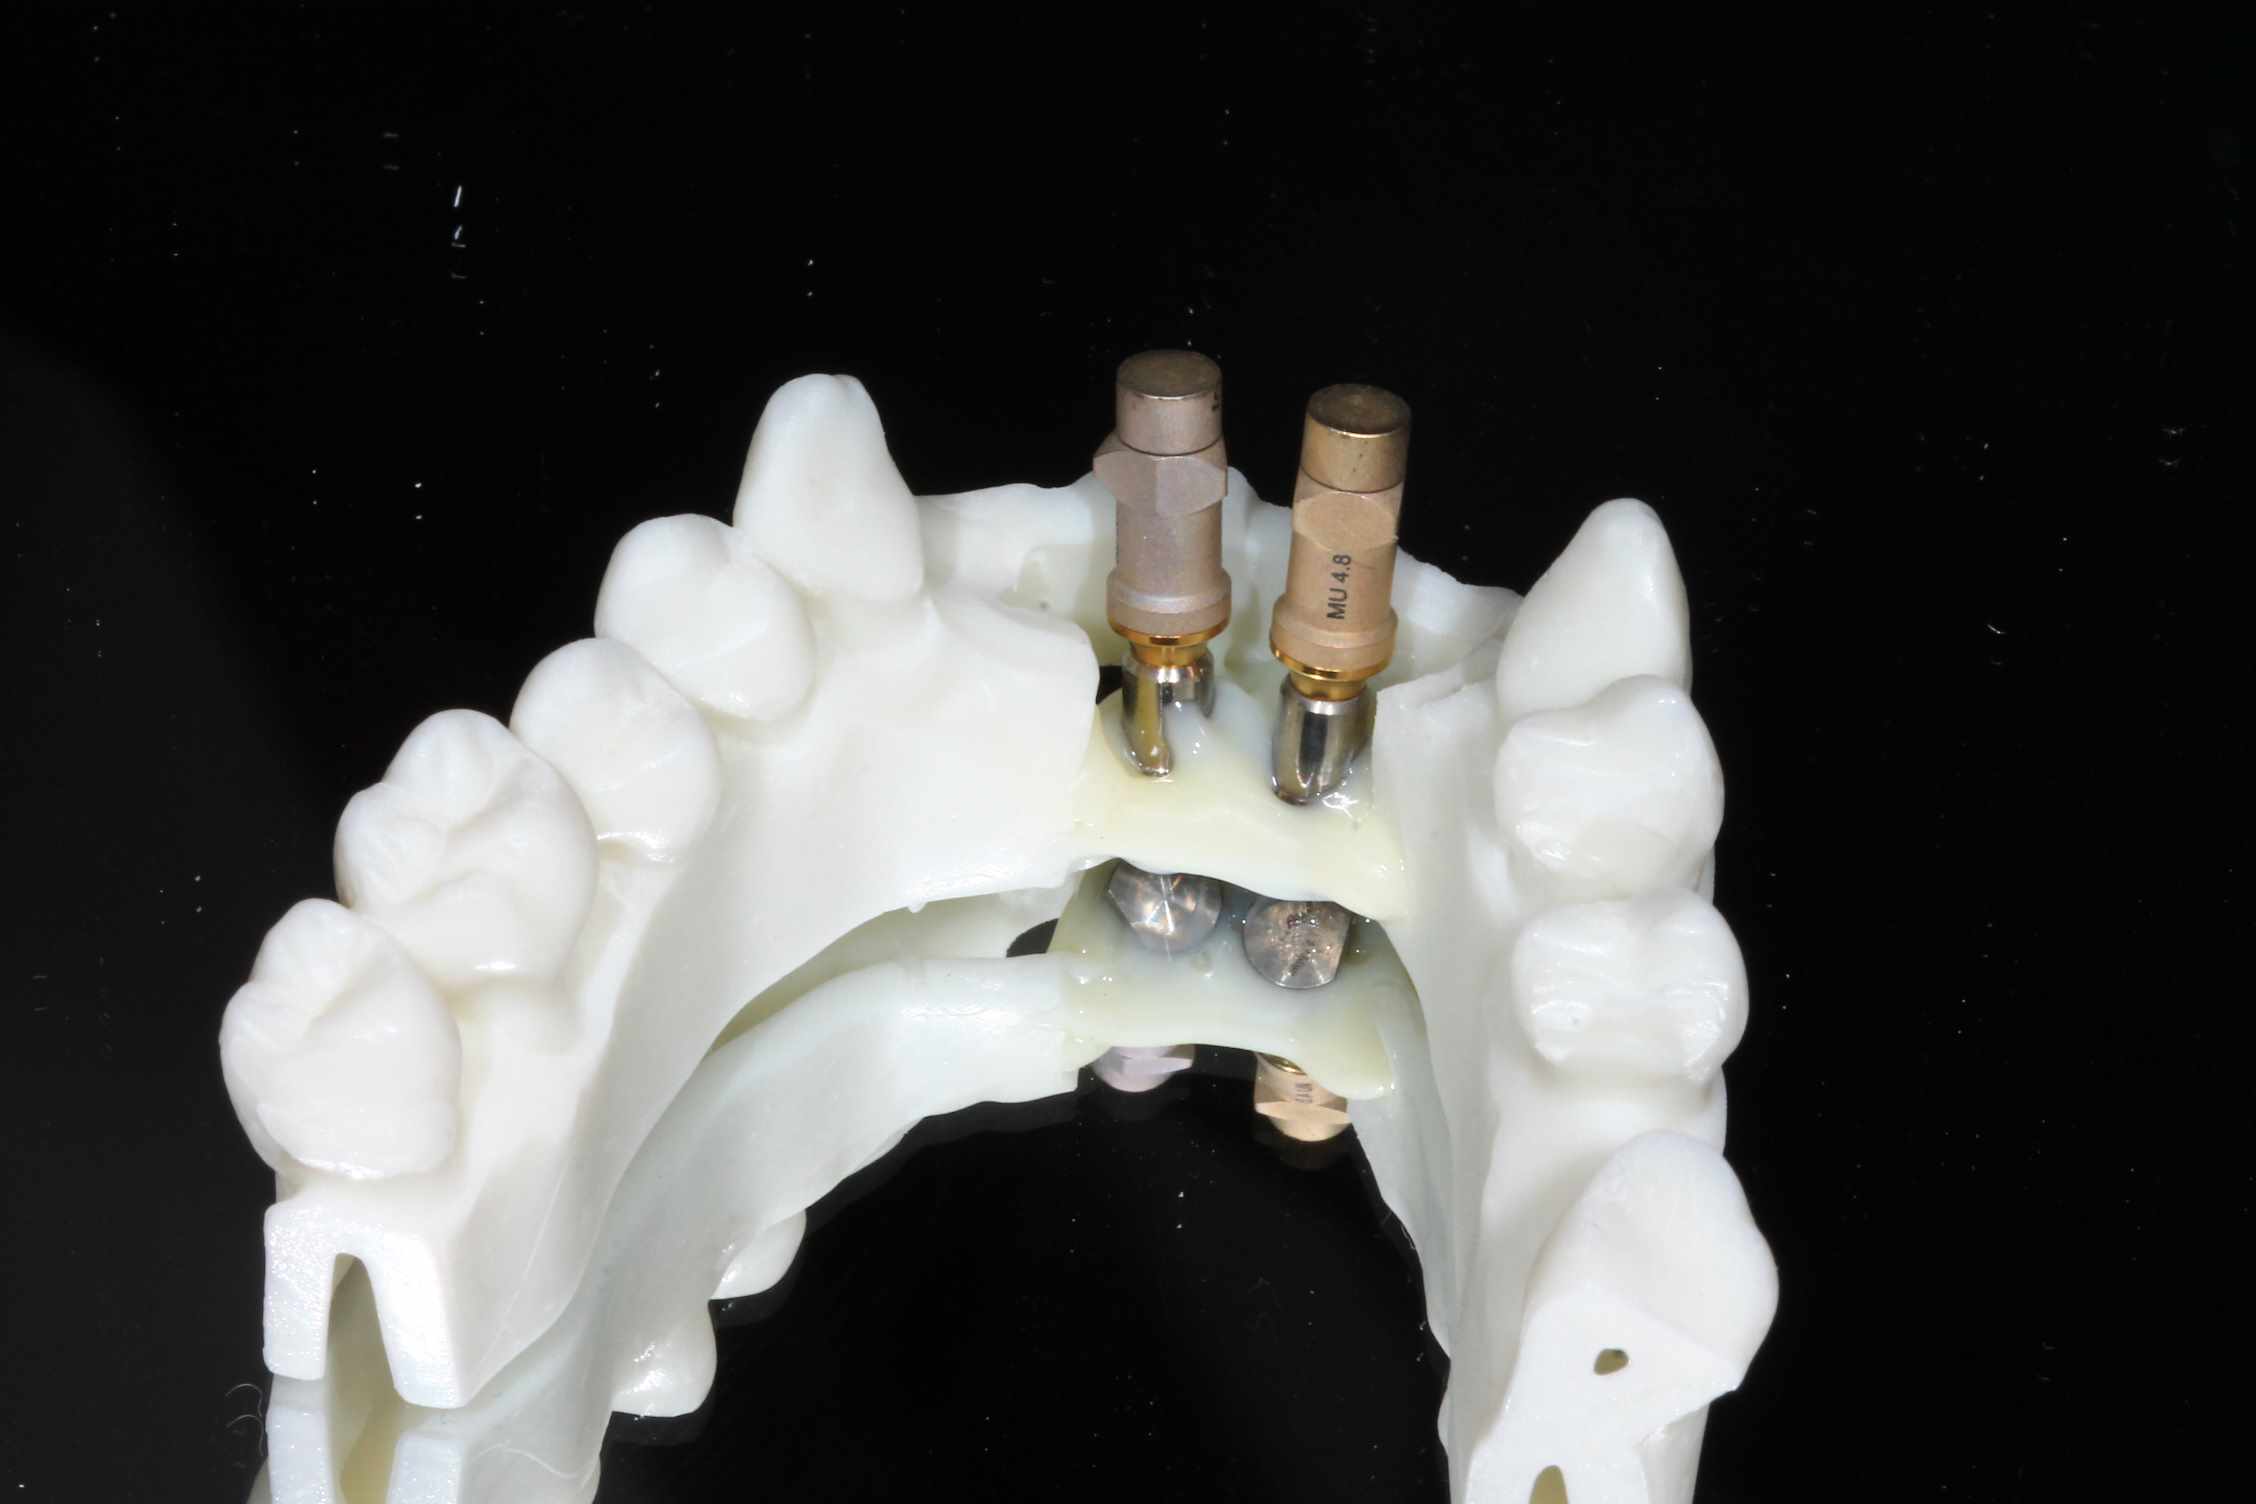

Mais celui la est tout chaud ( de vendredi dernier ) et j'ai regarder le temps que j'ai mis ( beaucoup plus complexe, donc plus long ). on va l'appeller Cas 2.

3 h de planif, modélisation du guide, puis 2 h environ pour la simulation de la chir , le modelisation et l'impression du bridge, qui tombe pile, zero retouche occlusale.

simulation de la chir. scan, matching des elements avec medit design, finition du bridge dana meshmixer.